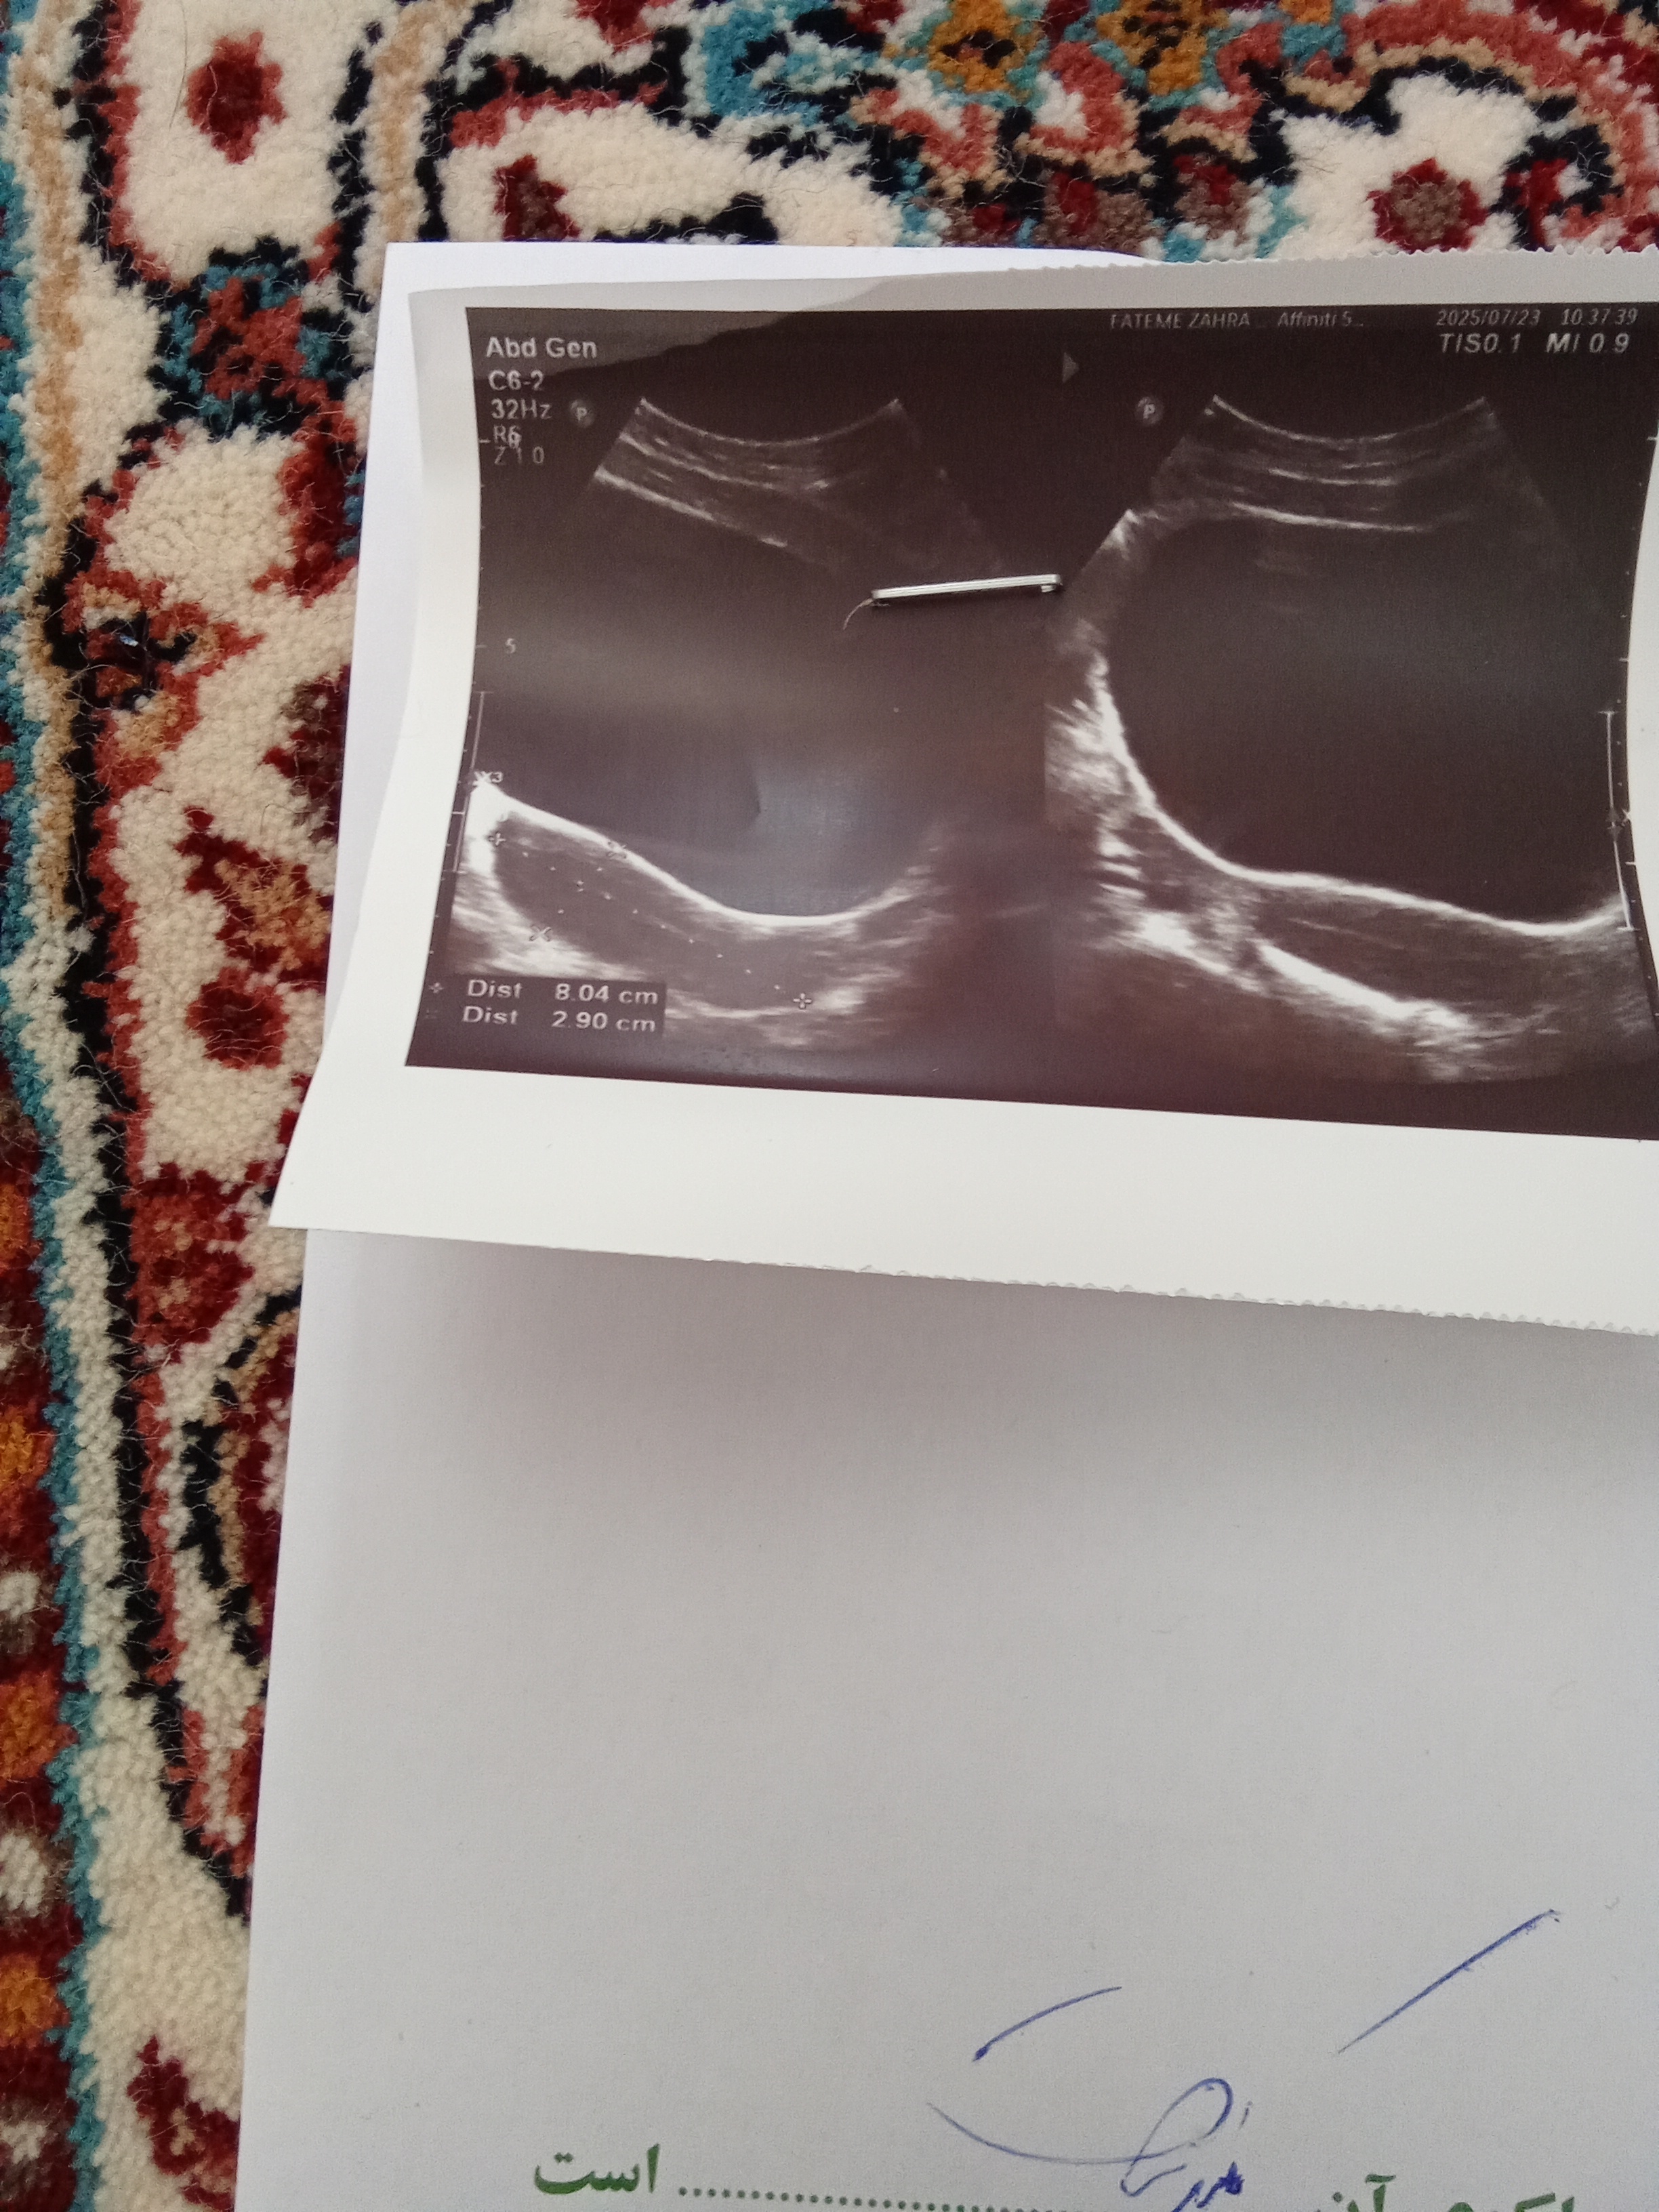

روز چندم پریودت رفتی که ضخامت رو زده ۲؟

بقیه اش طبیعیه

برا روز ۴ یه کوچولو کم هست

برای روز ۱۰ حدودن باید بین ۷ تا ۱۰ باشه فکرکنم

هنوز نرفتم پیش دکترم امروز سونو بود گلم

آهاااا ممنونم گلم برم پیش دکتر ببینم چی میگن توی سونو گفت که چیز خاصی نمی‌بینم اینا هورمونها بهم ریخته

این فقط سنوی رحم هست

یعنی تخمدان ها رو دقیق بررسی نکرده

چون پریودت دور شده ممکنه یه مقدار تنبلی تخمدان هم داشته باشی(جدا از بحث استرس که داری) که روی ضخامت رحم هم اثر گذاشته